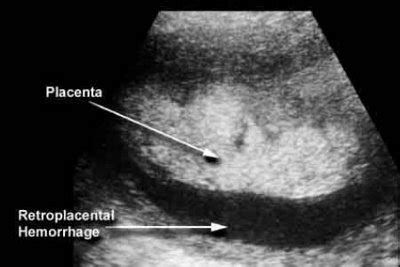

Il distacco di placenta è un’emergenza ostetrica che si verifica quando, prima del tempo, la placenta si stacca dalle pareti dell’utero. Evenienza che si concretizza raramente e in gestazioni già problematiche - a favorirla, per esempio, sono l’età elevata della madre e l’ipertensione - in acuto ha come sintomo un dolore improvviso, costante e localizzato. Il distacco intempestivo di placenta normalmente inserta può avvenire per cause meccaniche o traumatiche (cadute, traumi addominali, colpi di tosse violenta ecc.), malattie degli annessi fetali (polidramnio), cause di origine fetale o locale. Il mancato distacco della placenta, dopo l’espulsione del feto, nel periodo del secondamento, può essere determinato da deficienza delle contrazioni uterine (inerzia uterina) o da alterazioni del miometrio e della placenta (abnorme aderenza della placenta al miometrio). Gran parte delle complicanze ostetriche, fra cui aborti ricorrenti, il difetto di accrescimento del feto, la preeclampsia (gestosi), la sofferenza fetale, avvengono proprio per un deficit della placenta.